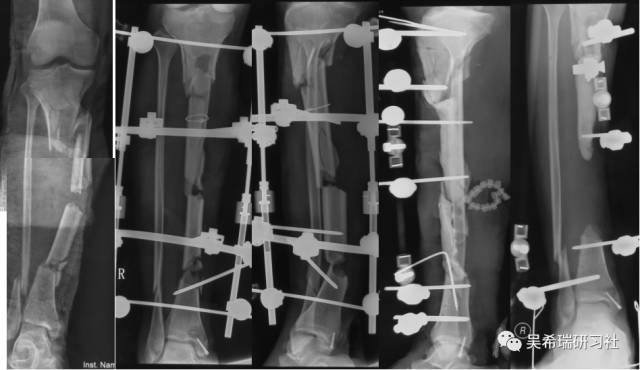

病例9

多发骨折车祸伤手术后继发感染,大段骨缺损

去除死骨——骨水泥——植皮

骨搬移

4个月

9个月

剥削植骨

TIPS:开放植骨+针式牵引骨搬移骨水泥Spacer/骨水泥链珠技术剥削植骨技术皮肤牵张技术胫跖骨牵引技术尽早下地走路刺激骨生长,改善骨质量历时2年